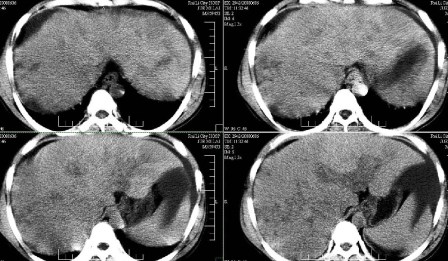

标题: CT13930:M,33岁,腹胀、腹痛10天余。 [打印本页]

标题: CT13930:M,33岁,腹胀、腹痛10天余。

右上腹压痛,肝大,质硬。腹水征。ct:肝右叶(后段)低密度影,性质待定。

肝硬化、腹水,肝右叶低密度首先考虑肝癌可能,左叶低密度不除外转移可能。建议增强检查。

肝硬化、大量腹水,肝右叶巨大肿块,境界欠清,中间见不规则低密度坏死区,考虑肝癌应该问题不大,至于肝左叶低密度灶是否转移应该意义不是很大了,慎重起见还是建议增强扫描。